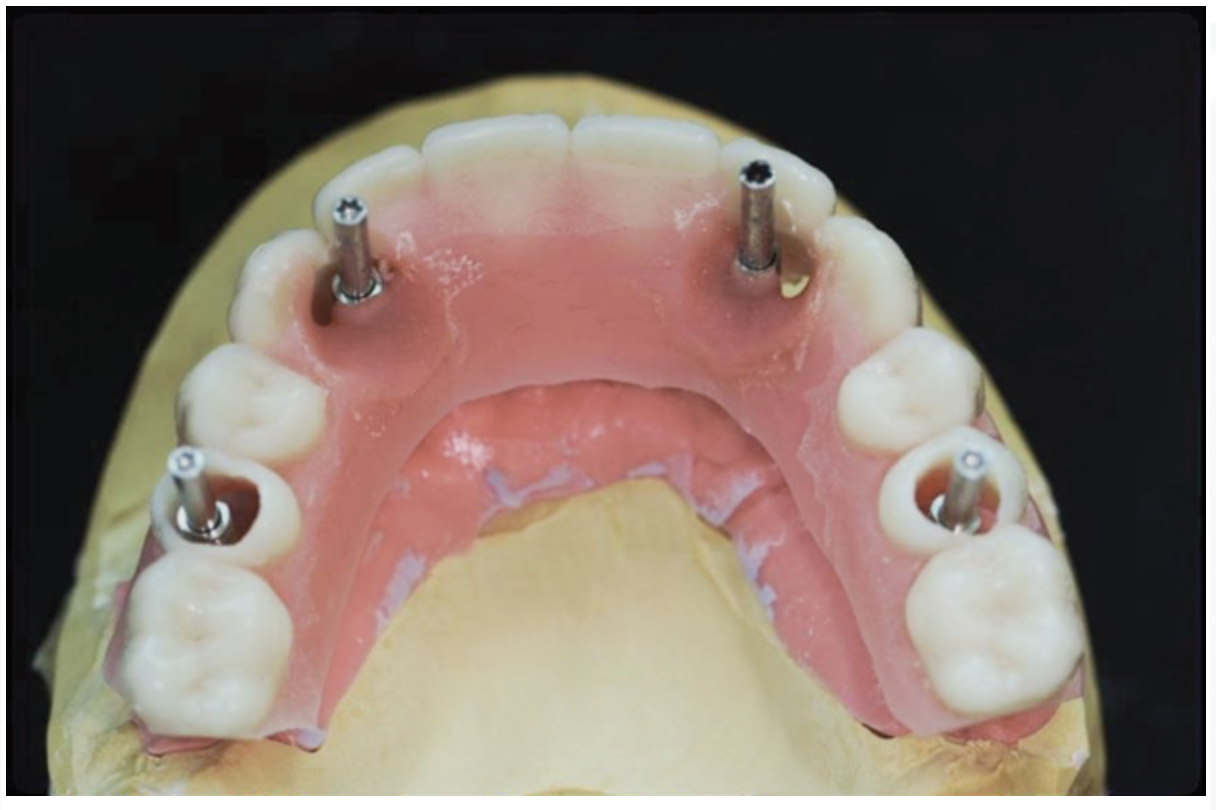

To start, a surgical impression is performed. Open-tray impression copings are secured to the restorative abutments, and a denture-strengthening bar is attached to the copings using a low-expansion pattern resin. The “salt and pepper” technique is used for precise control of the material, thereby avoiding contact with the surgery site and more effectively controlling working time. A plastic impression tray is modified in the occlusal areas where the impression copings will emerge and is tried-in to verify that there are no interferences. Polyvinylsiloxane impression putty is mixed and adapted over the impression copings and denture-strengthening bar. Impression material is also placed in the tray prior to seating. The impression coping screws are exposed and disengaged, allowing the impression to be easily removed. Rigid stabilization of the copings in the impression is verified (Figure 10 through Figure 12). The surgical index is performed using the same provisional prosthesis guide used during the surgery. Only the two anterior implants are indexed. The provisional prosthesis guide is seated to verify the absence of interferences with the two anterior temporary cylinders, and cold-cure acrylic material is applied through the access windows using a “salt and pepper” technique (Figure 13). The prosthesis is held in place with light pressure on the prosthesis guide over the palate or the posterior lingual mandibular ridge until the resin is cured. The VDO is verified after guiding the patient into occlusion with a bite registration recorded in the lab. Esthetic and functional parameters are verified, and the indexed prosthesis is removed with the attached temporary cylinders, and it is then disinfected in cold sterile solution.

Fig 10. Surgical impression—Open-tray impression copings are secured and splinted with a denture-strengthening bar using low-expansion pattern resin.

Figure 10

Fig 12. Surgical impression—After impression putty is adapted around the impression copings and bar, the tray is filled with impression material and seated, the copings are exposed, and the retention screws are disengaged to allow the impression to be easily pulled.

Figure 12